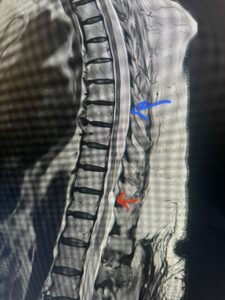

Fig. 1 Sagittal T2-weighted thoracic MRI demonstrating both T10-11 focal intradural arachnoid cyst (red arrow) and larger upper thoracic cyst that appears to extend from T4-T8 (blue arrow).